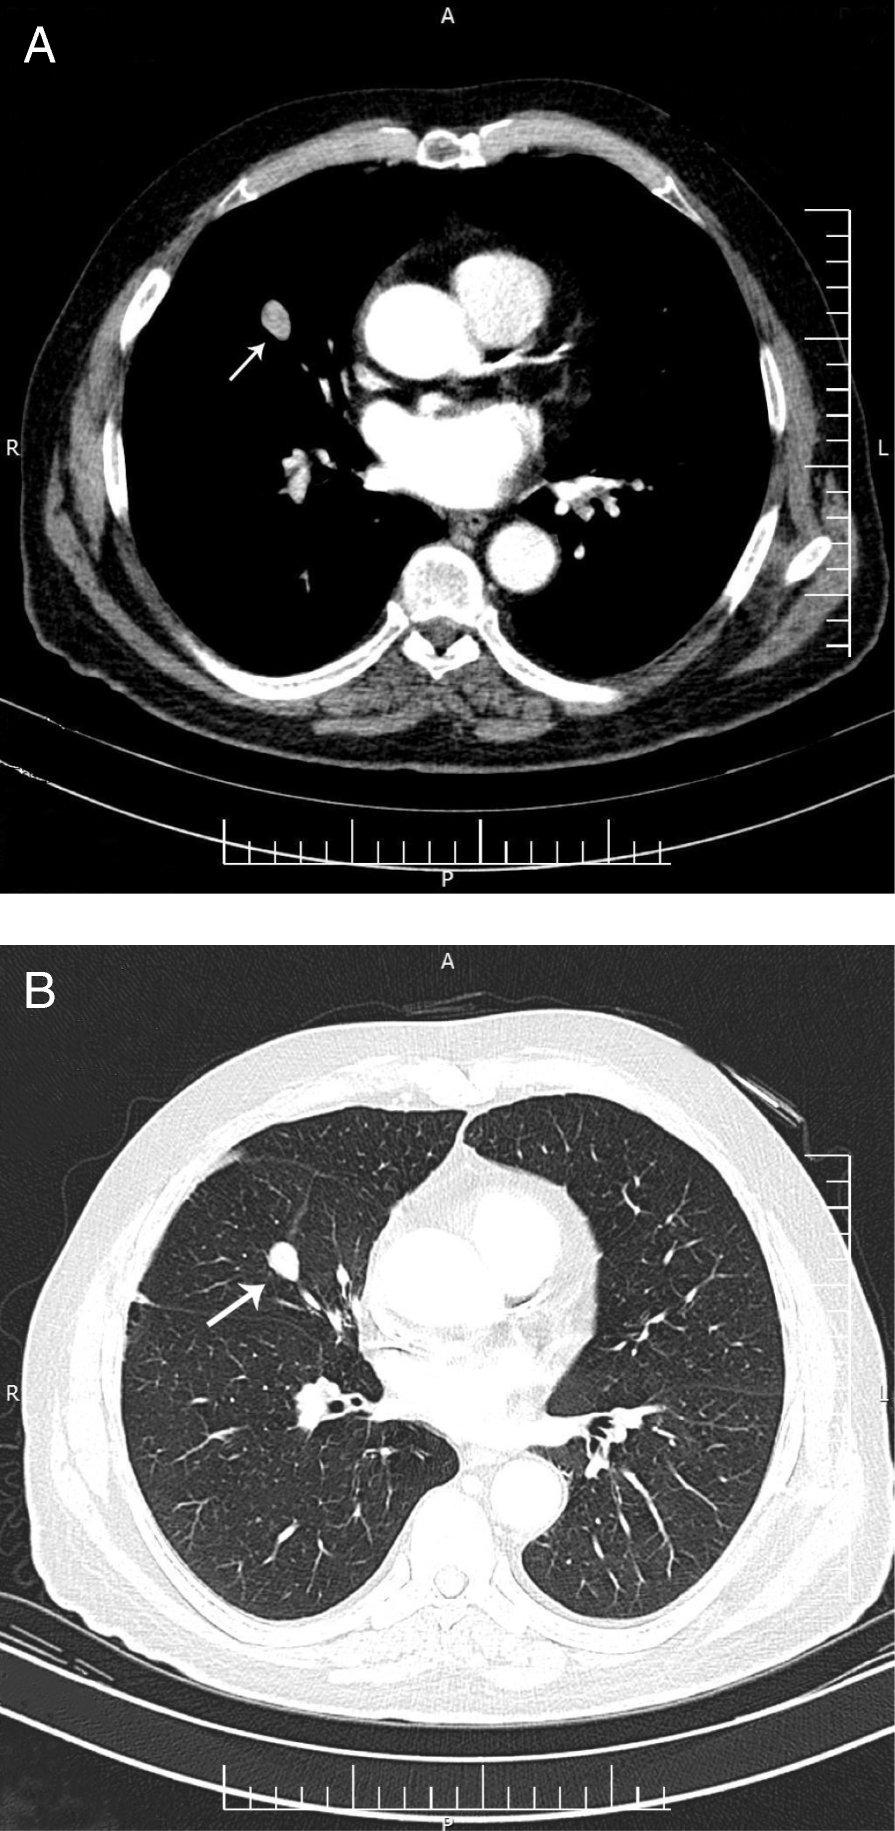

Fig. 2From: Recurrence of a neuroendocrine tumor of adrenal origin: a case report with more than a decade follow-upSpiral chest computed tomography of the patient in 2017. a mediastinal view, b parenchymal view of lung nodule (arrow)Back to article page